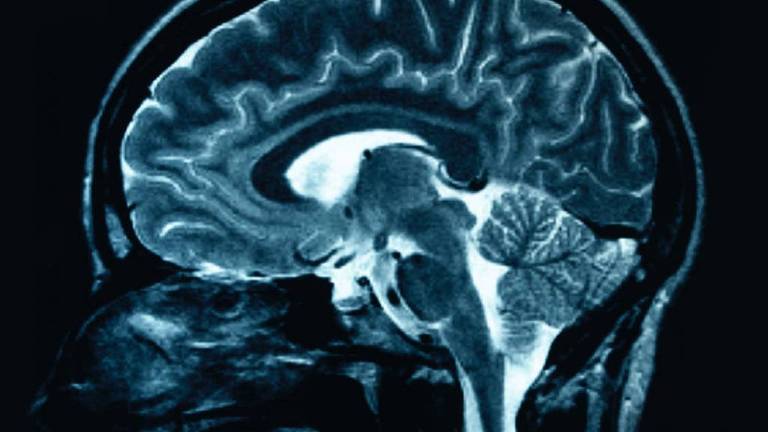

El DIPG (siglas en inglés) suele afectar a niños de entre cuatro y nueve años, los cuales pierden paulatinamente el control muscular a medida que el tumor ataca, con rapidez, el puente o protuberancia, una región del tronco encefálico que conecta el cerebro con la médula espinal.

Este tipo de tumor es difícil de alcanzar y eliminar quirúrgicamente y, a pesar de los tratamientos con radiación, normalmente los niños no suelen sobrevivir más de nueve meses y menos de un uno por ciento lo hace más de cinco años.